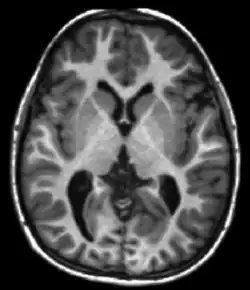

T1 is significantly different between grey matter and white matter and is used when undertaking brain scans. A strong T1 contrast is present between fluid and more solid anatomical structures, making T1 contrast suitable for morphological assessment of the normal or pathological anatomy, e.g., for musculoskeletal applications.

T1ρ MRI has been used to image tissues such as cartilage,[4][5] intervertebral discs,[6] brain,[7][8] and heart,[9] as well as certain types of cancers.[10][11]